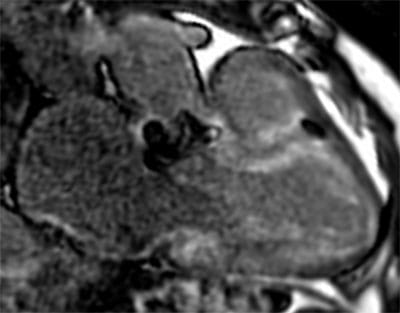

• Dedicated state-of-the art Cardiac MRI and CT imaging program (1.5T Siemens Aera; Dual-Source Siemens Force, Siemens Drive, and Flash scanners) with dedicated CMR techs and CT techs.

• High volume program with daily case averages of 10 CMR studies and 25-35 cardiac CTAs (50% coronary CTA, 30% structural, 20% other). Broad case complexity, including CAD, structural heart pathologies, congenital heart disease,  and implantable devices. Routine use of cutting edge technology, including T1/ECV mapping, quantitative perfusion, free-breathing CMR exam, artificial intelligence based CT analyses, CT-FFR, structural planning and simulation.